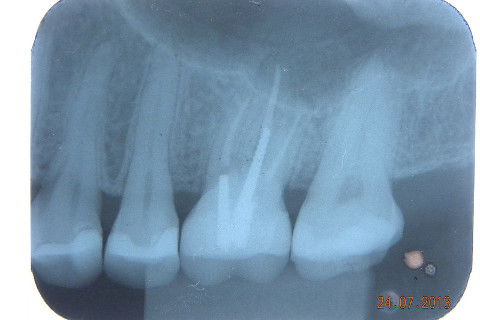

FOTO DE OUTRO CASO IGUAL. Até radiograficamente existe o "biomimetísmo"

Caso de fratura de um trabalho protético preexistente, não sei qual e nem o paciente soube informar. Na minha opinião caso indicado para pinos metalicos rosqueáveis, muitos colegas condenam e indicam para esse caso pino metálico fundido. Creio que o fato de você fazer o preenchimento do núcleo com resina e depois cimentar com um cimento resinoso onde vai haver adesão química nas duas partes, formando um corpo único entre núcleo e coroa, ofereça uma resistência muito maior do que uma linha de cimentação onde a retenção é apenas mecânica. Continuando... 1ª CONSULTA: Pinos metálicos rosqueáveis, preenchimnto em resina, coroa provisória e moldagem com sil de adição (para qe possamos vazar o troquel e no mesmo molde o modelo para aplicação da cerâmica. 2ª CONSULTA: restauração de uma cárie no dente 17 (eu sei que era para ter feito na 1ª consulta por conta do ponto de contato, mas não deu tempo) e cimentação com cimento resinoso da 3M e caso encerrado. A radiografia não é desse caso, mas de uma caso igualzinho, a única diferença foi que envolveu cirurgia periodontal, veja como há a formação de um corpo único entre, núcleo e coroa. Um abraço. Jadson.